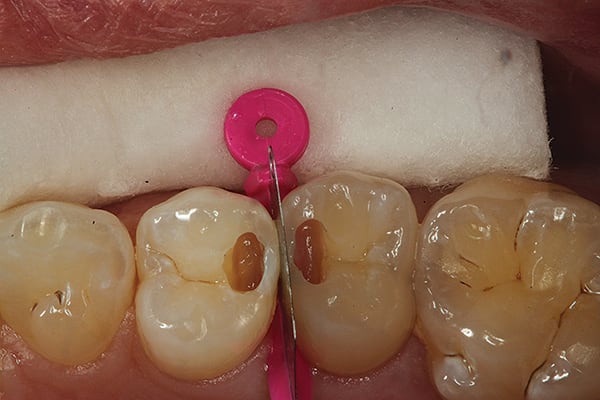

3. The tunnel preparations have now been completed. Note the affected dentin present but no decay.